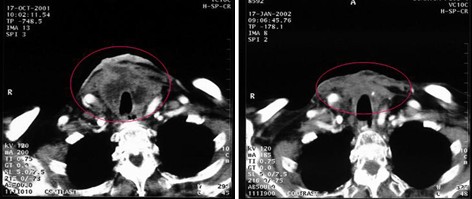

女性,69歲,甲狀腺癌,術(shù)后9個月局部復(fù)發(fā),放療、化療、熱療均失敗,腫瘤壓迫氣管及頸前皮膚形成的癌痂造成呼吸困難。治療前CT顯示頸前腫瘤22.5cm2。治療方案:今又生腫瘤內(nèi)注射今又生1×1012VP/次/周×8;聯(lián)合淺部熱療。結(jié)果:治療后1月,頸前腫瘤縮小到11.7cm2,縮小了48%,壓迫氣管的癌痂脫落,呼吸困難的癥狀完全緩解。

治療前

治療后